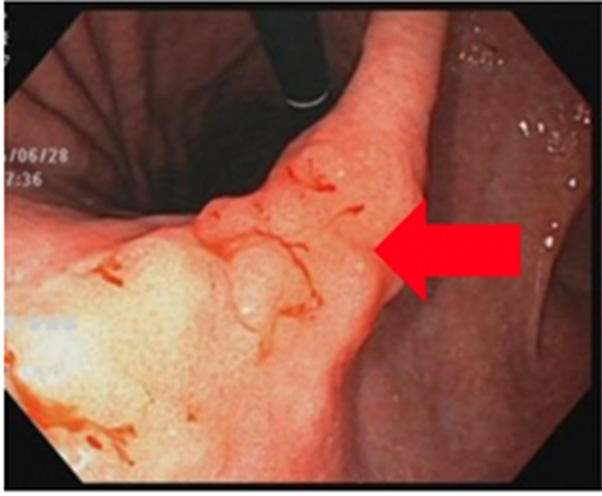

早期大腸癌

内視鏡で発見しました。

その場で切除しました。